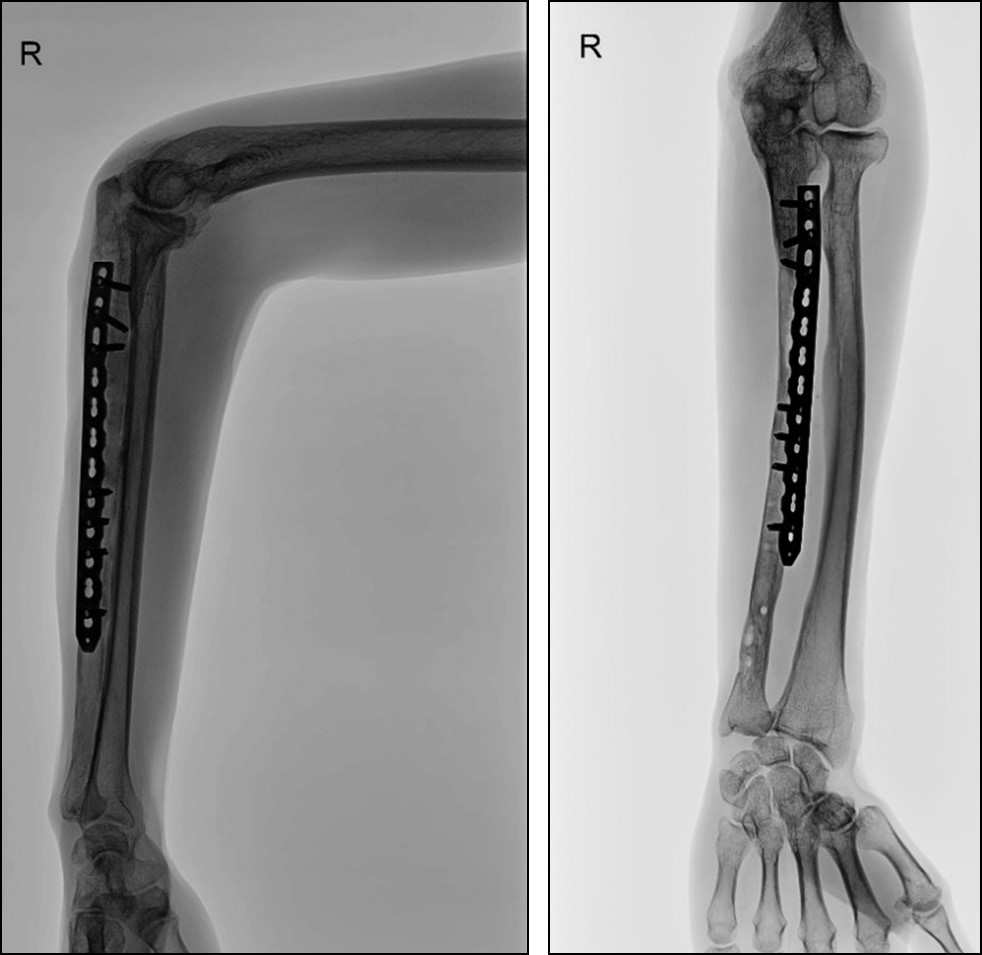

Рис. 4. Рентгенограмма правого предплечья после аутопластики костного дефекта губчатым трансплантатом и остеосинтеза пластиной.

Fig. 4. Radiograph of the right forearm after cancellous bone grafting and plate osteosynthesis.

На рентгенограммах правого предплечья в двух проекциях через год, после второго этапа оперативного лечения, определяется полноценная костная перестройка трансплантата и сращение локтевой кости (рис. 6).

Рис. 6. Рентгенограммы правого предплечья через 1 год после реконструкции.

Fig. 6. Radiographs of the right forearm one year after reconstruction.